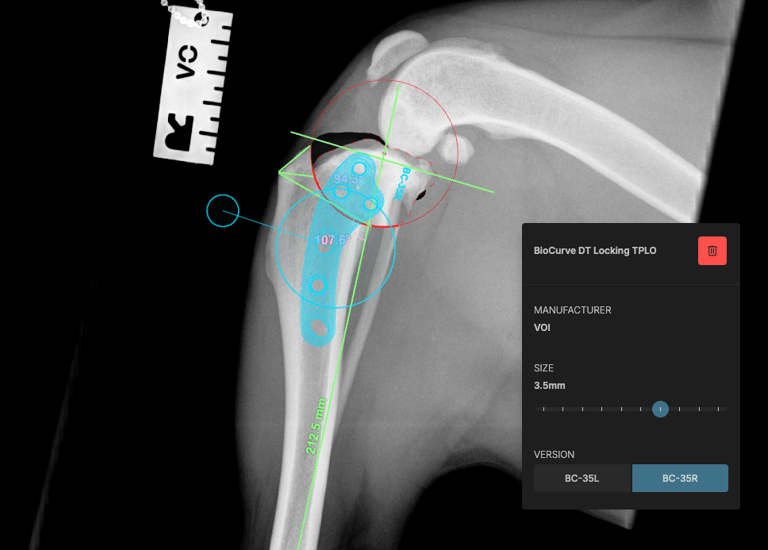

The surgical plan was developed using specialized veterinary orthopedic planning software, which allowed for precise measurements and implant selection, ensuring optimal execution of the surgical procedure (Figs. 3 and 4).

Preoperative measurements indicated a tibial plateau angle (TPA) of 25°. A TPLO saw blade size 24 was used, achieving a rotation of 8.3 mm. Pre-surgical measurements were: A = 11 mm, B = 13 mm, and C = 35 mm.

A 3.5 mm TPLO locking plate was placed with two compression screws. A 2 mm anti-rotational pin was left in situ, as it did not interfere with the placement of the proximal fragment screws.

Fig. 4